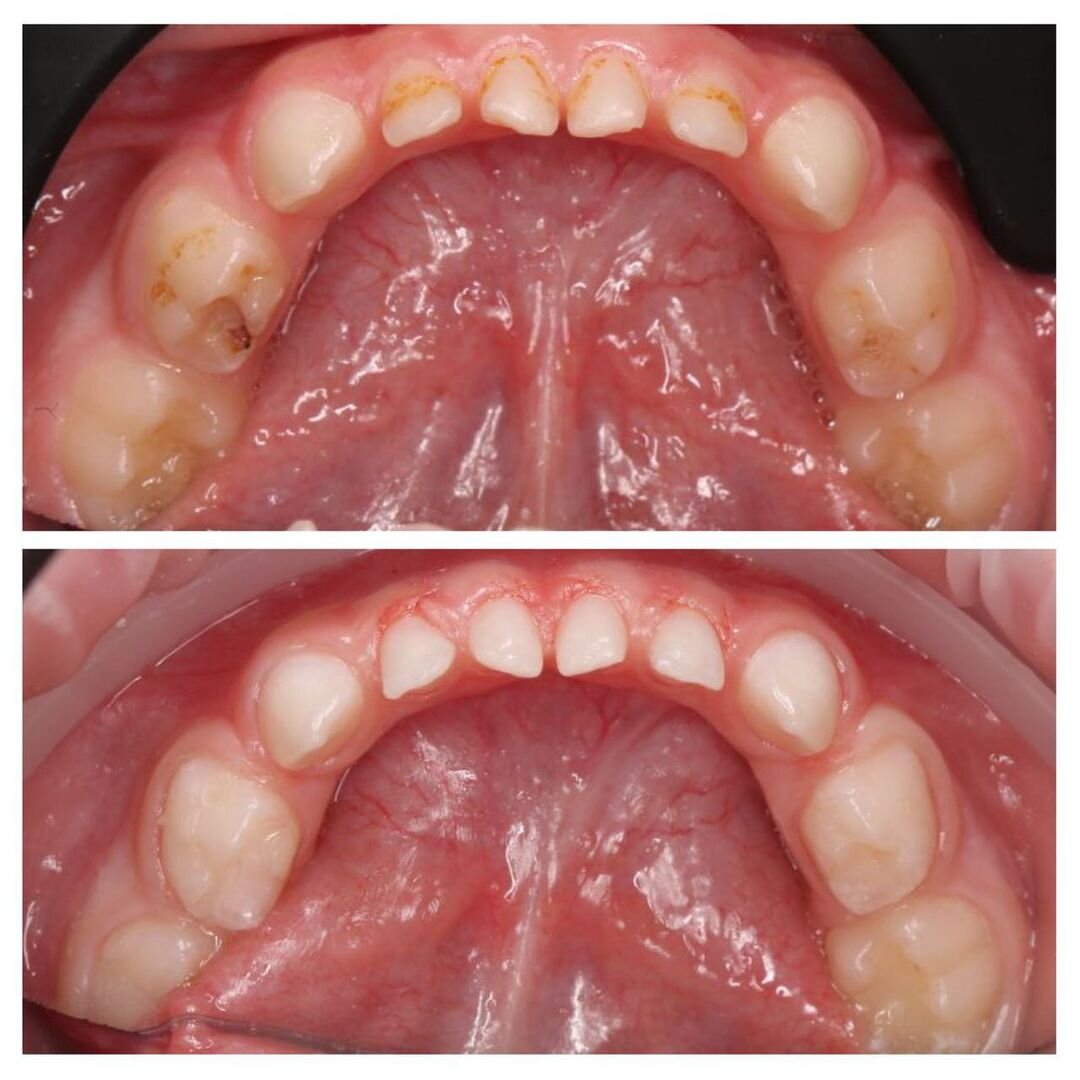

Лечение 16 молочных зубов за одно посещение!

Верхние резцы прорезываются одними из первых и страдают сильнее всего.

Наглядный пример — наш маленький пациент.

Ему всего 2,5 года, а от четырех верхних резцов практически ничего не осталось.

Всё «съел» кариес❗

Кроме резцов пострадали практически все остальные зубы.

К сожалению, у кариеса нет приоритетов — где условия позволяют, там и появляется.

Малыша лечили под наркозом.

А теперь внимание, сколько зубов было поражено?

ШЕСТНАДЦАТЬ!

❗16 зубов вылечила за 4 часа наш детский стоматолог Мария Штельмах!

• Сделано 8 реставрации;

• Вылечен 1 пульпит и 4 кариеса;

• Загерметизированы 3 зуба.